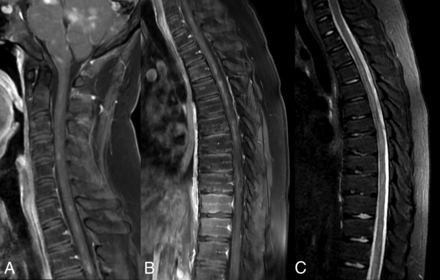

Initial CT images obtained at the outside institution demonstrated patchy areas of hypoattenuation centered around the dentate nuclei of both cerebellar hemispheres. MR imaging demonstrated extensive multifocal T2-hyperintense signal abnormalities and regions of poorly marginated patchy enhancement. These were predominantly located in an almost symmetric distribution in the midbrain, dentate nuclei, and cerebellar peduncles (Fig 1). None of the abnormalities demonstrated restricted diffusion. There was a mild local mass effect associated with these findings, without obstructive hydrocephalus. Lesser involvement was observed in the periatrial white matter and optic chiasm. The pituitary infundibulum was thickened and demonstrated prominent enhancement. In the spine, similar T2-hyperintense enhancing abnormalities were seen throughout the cervical and thoracic cord (Fig 2). A whole-body PET was performed to evaluate a systemic disorder, which revealed FDG uptake in the distal femoral diaphysis with increased intramedullary density on the corresponding CT images.

MR imaging of the cervical (A) and thoracic (B and C) spine demonstrates numerous patchy areas of enhancement along the cervicothoracic cord (A and B). Corresponding fat-saturated STIR images of the thoracic spine demonstrate multifocal T2 hyperintensities in these regions (C).